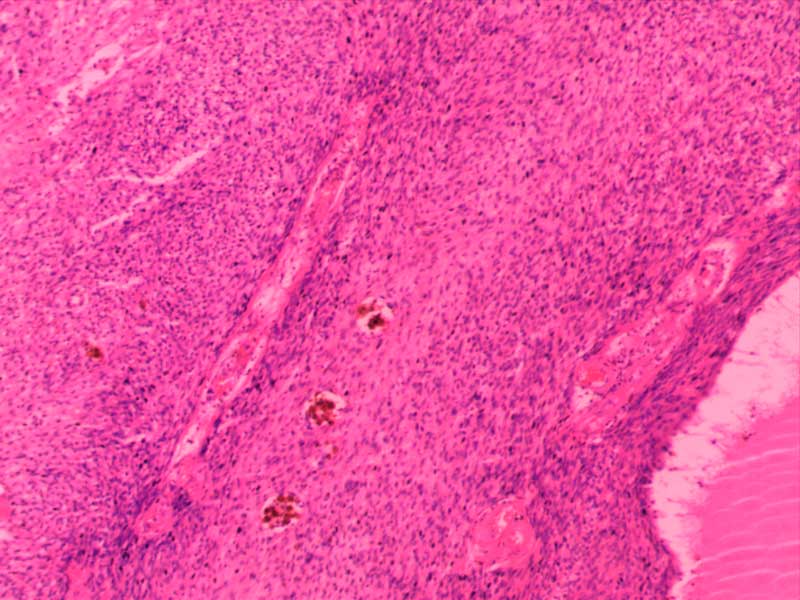

神经鞘瘤-10倍

肾透明细胞癌-10倍

肾细胞水肿-4倍

粟粒性肺结核

透明血栓-10倍

纤维肉瘤10-倍

纤维素性胸膜炎

小叶性肺炎-10倍-(2)

新月体肾炎-(2)

异物性炎-10倍

主动脉粥样硬化-4倍

主动脉粥样硬化-10倍